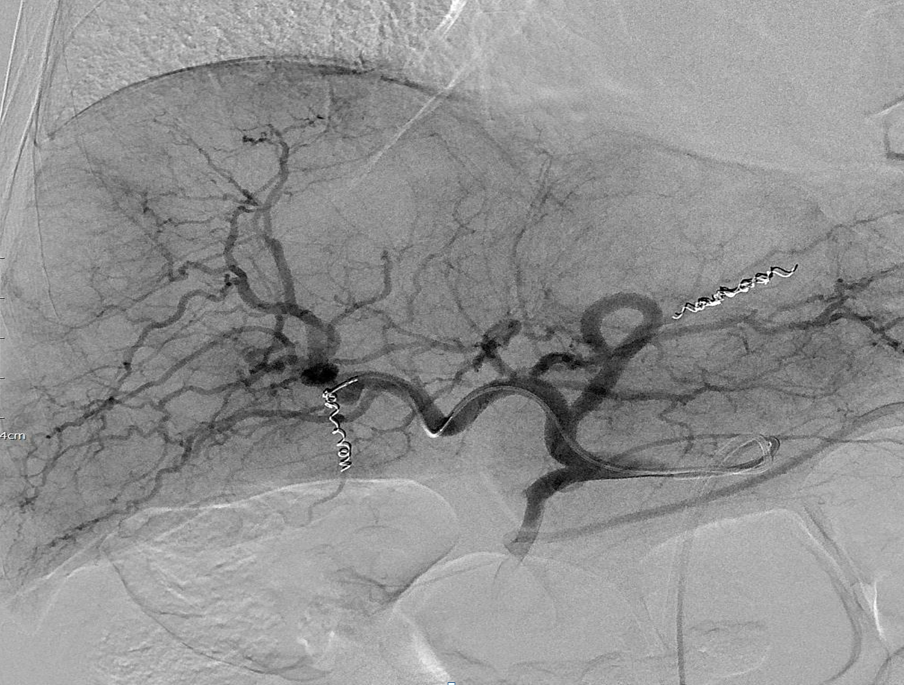

방사선색전술은 고전적인 간동맥화학색전술(TACE)과 시술 방식은 같지만 혈관에 항암제대신 방사선 물질을 투여한다. 여기에는 베타선을 방출하는 방사선 동위원소인 이트륨(Yttrium)을 사용한다. 이 약물은 선택적으로 종양 조직에 축적돼 베타선 방출을 통해 종양괴사를 유도한다.

서울의대 김효철 교수(영상의학과)는 "방사선색전술에 효과적인 환자를 잘 찾아 연구를 수행해야하는데 실제로 이런 연구는 매우 드물고, 게다가 혈관끝을 찾아 접근하는 색전술 특성상 의사들의 테크닉이 좋아야하는데 이런 부분 때문에 연구가 일관적이지 않다"고 말했다. 현재 여러 연구가 있지만 효과가 좋다는 연구와 동등하다는 연구가 혼재돼 있다.

김윤준 교수는 "방사선 노출을 예방하기 위해 폐흡입반응을 확인하는 약물주입과정이 필요하고, 다른 장기로 연결되는 혈관에 방사선 약물 침범을 막기 위해 혈관을 막는 사전 조치도 이뤄져야한다"며 "과정이 필요할 뿐이지 실제 시술시간은 큰 차이가 없고, 무엇보다도 서울대병원에서는 아직까지 관련 부작용은 없었다"고 말했다.